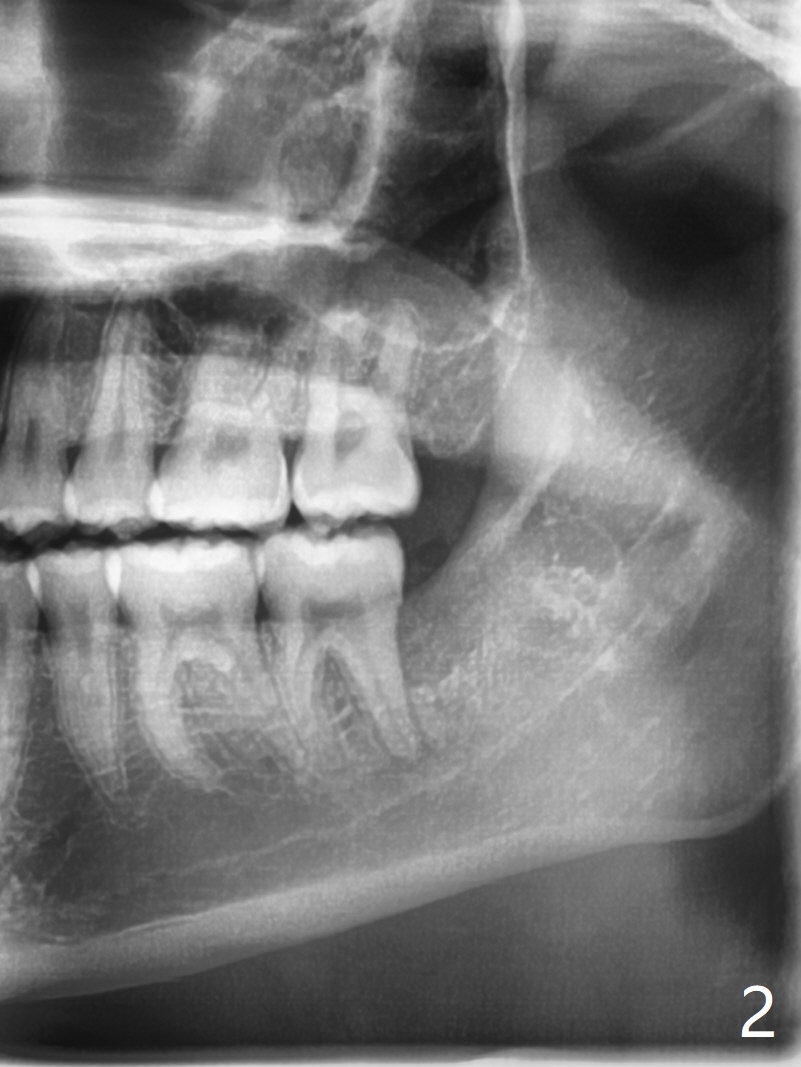

A 15.5-year-old woman with poor oral hygiene has pericoronitis at #17 extending to the left 2nd molar, corresponding to bone loss between them (Fig.1 ^). After extraction, a piece of Osteogen plug is placed horizontally as mesial as possible (Fig.2).